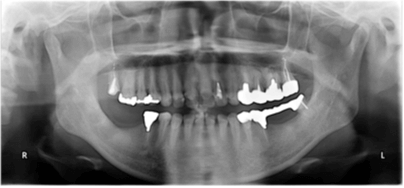

パノラマレントゲン写真

-